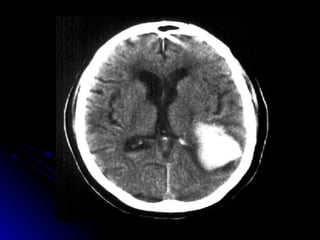

HEMORRAGIA

AVE HEMORRAGICO

“Cuadro causado por

rupt ur a vascular e

irrupción de sangre en el

parénquima cerebral,

acompañado de

hipert ensión endocraneana

y por lo gener al

AVE Hemorrágico

Frecuencia15%

Edades: hombres50-70 años

( 16% antesdelos45)

Mortalidad: 20%, aumentacon

Clasificación HemorragiaCerebral

Iº Gran hemorragiaClásica

IIº HematomaIntraparenquimatoso

1) Profundo 60%

2) Superficial 20%

3) Cerebelo <15%

4) Tronco <5%

IIIº HemorragiaSubaracnoidea 5-10 %